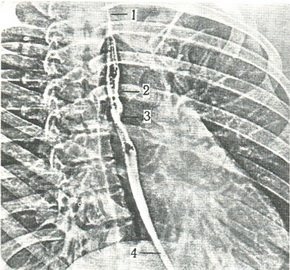

229. Электрорентгенограмма грудної клітки в першій косій проекції. Стравохід контрастирован (за Н. Р. Палееву). 1 - шийне звуження; 2 - звуження на рівні дуги аорти; 3 - звуження на рівні бронха; 4 - нижнє звуження. |